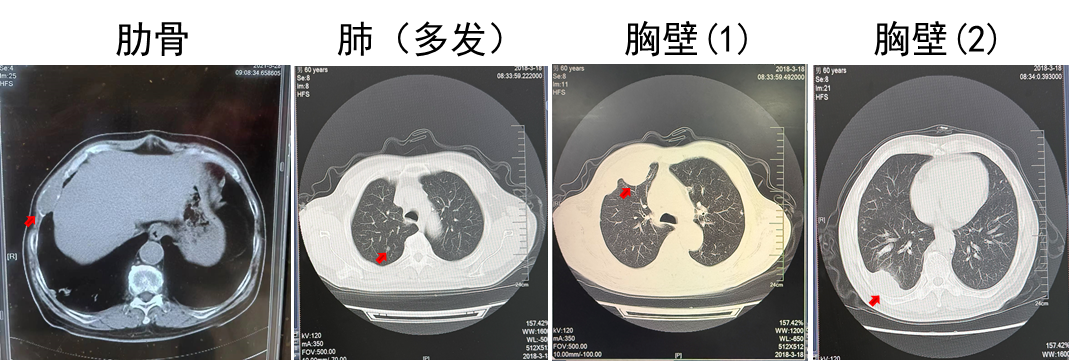

2018.03 PET-CT提示多发肺转移,肋骨转移

2018.03.22胸壁穿刺显示转移性癌,考虑肾来源

诊断为T2N0M1,IV期,IMDC低危

2018.03.22舒尼替尼50 mg QD。肋骨肿瘤注射唑来膦酸3周1次(共3次),同步放疗3 Gy(共10次)。

疗效:肋骨病灶疾病稳定(2年),肺部病灶部分缓解(2年)。